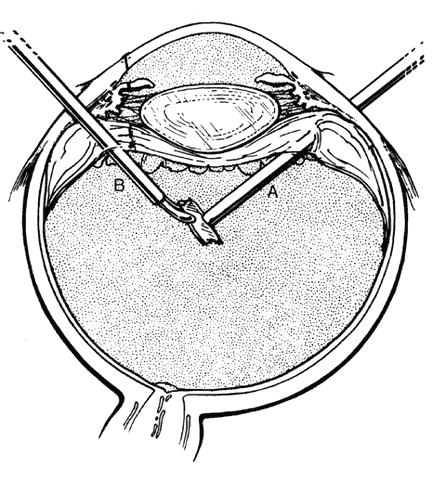

hemorrhage, retinal breaks, and retinal detachment. SUBLUXATION OR DISLOCATION OF THE LENS Minor degrees of subluxation should be suspected when phakodonesis or iridodonesis is noted. Zonular rupture is certain if there is vitreous prolapse into the anterior chamber. In the absence of cataractous changes and related visual impairment, treatment is not indicated. A subluxated, cataractous lens can be removed by aspiration-irrigation or phacofragmentation through a limbal incision, but complications may occur, including posterior dislocation of the lens or lens fragments, vitreous prolapse and incarceration, and vitreous aspiration with resultant vitreous base traction and retinal tear formation. Also, visualization of the anterior vitreous by coaxial illumination is poor compared with fiberoptic endoillumination. These problems make pars plana lensectomy an attractive alternative. Bimanual techniques permit fixation and simultaneous removal of the lens by the vitreous suction-cutter, if the lens is soft, or phacofragmentation if it is sclerotic (Fig. 1A). Posteriorly dislocated fragments can be removed safely, with minimal vitreous traction, using the same incisions and instruments (see Fig. 1B). With endoillumination, prolapsed and juxtalenticular vitreous is readily identified and excised with the vitrectomy probe. Without question, pars plana lensectomy is the preferred method for removing a completely dislocated lens. The technical aspects of dislocated lens and lens fragment removal are described elsewhere in these volumes. VITREOUS HEMORRHAGE Blood in the vitreous may come from tears in the iris, ciliary body, choroid, or retina. Hemorrhage from choroidal ruptures accumulates beneath the neurosensory retina; it then passes through the retina into the vitreous without necessarily causing a retinal break. Regardless, it is important to assume that a retinal break is present until proved otherwise. Vitrectomy is indicated for vitreous hemorrhage caused by ocular contusion when a retinal detachment is suspected because of sudden additional loss of vision, when a retinal detachment is detected through a window in the hemorrhage, when a large retinal break or retinal detachment is diagnosed by ultrasound, or when there is no improvement after a reasonable period of observation. Preoperative contact A-scan and B-scan ultrasonography is helpful for detecting posterior vitreous detachment and differentiating it from retinal detachment. It is dangerous, however, to rely completely upon the accuracy of ultrasound. The presumed posterior hyaloid should be approached with caution until it can be identified with certainty. A standard three-port vitrectomy technique is preferred for nonclearing vitreous hemorrhage. Initially, a central core of opaque vitreous is removed, beginning sufficiently close to the lens that the tips of the cutter and endoilluminator can be visualized. The excision is carried posteriorly, removing successive layers of hemorrhagic and fibrinous vitreous, until the anticipated plane of the posterior hyaloid is approached. A constant surveillance is maintained for a gray membrane containing radially oriented vessels (undiagnosed detached retina). A small opening is made in the detached posterior hyaloid, through which unclotted blood is aspirated by use of active suction from a soft-tipped cannula. Once the retina has been visualized, it is best to remove as much retrohyaloid blood as possible to prevent dispersion into the vitreous cavity with consequent loss of visual control. If the posterior vitreous cortex is not detached, it can be separated from the retina by gentle suction with a soft-tipped cannula at the edge of the optic disc. The elevated cortex is penetrated with a hooked needle or myringotomy blade, creating a window through which a pick is introduced to enlarge the area of cleavage. With the plane between hyaloid and retina established, the surgeon attempts to remove the entire cortical vitreous except for the firmly attached portion at the anterior vitreous base. Cortex that does not separate with gentle manipulation is isolated from surrounding vitreous to eliminate traction on the retina. It is important to remove the cortical vitreous from areas adjacent to retinal breaks. Failure to do so may result in subsequent tangential traction and retinal detachment. A scleral buckle should be considered if retinal breaks cannot be freed from surrounding vitreous cortex. The placement of sclerotomies close to the 3 o'clock and 9 o'clock positions facilitates maximal excision of the hemorrhagic anterior vitreous skirt, thereby improving visualization of the peripheral retina and pars plana. With use of coaxial illumination and scleral depression, the peripheral vitreous on the temporal side of the globe is trimmed with the cutter placed in the temporal sclerotomy, reaching both the superior and inferior quadrants, after which it is transferred to the nasal sclerotomy, and the process is repeated. The fiberoptic endoilluminator may damage the lens if used internally to illuminate the peripheral vitreous on the opposite side of the globe. However, the cone of light from the probe may be directed through the cornea to augment or replace the coaxial light source. Hemorrhagic retrolenticular vitreous can be stripped from the posterior capsule of the lens by gentle aspiration into the cutting port followed by withdrawal of the probe and simultaneous activation of the cutting mode. This technique is dangerous in young children because the retrolenticular vitreous is adherent to the lens, which is sufficiently pliable for aspiration into the port with consequent cataract formation. When the lens is clear, the process of removing peripheral and retrolenticular vitreous is less important than preserving lens integrity in most cases. It is important to expose the peripheral retina and vitreous base because most retinal breaks caused by ocular contusion are located in this area.2 All retinal breaks should be treated. Endolaser is used for posterior breaks, whereas peripheral breaks are treated with indirect laser assisted by scleral depression or transscleral cryoretinopexy. Cryotherapy is preferred when residual opaque vitreous partially obscures the targeted break. Encircling scleral buckles are not necessary after vitrectomy for nonclearing vitreous hemorrhage caused by ocular contusion when a clear view of the fundus periphery reveals no peripheral retinal tears or signs of traction, such as vitreous base avulsion. Similarly, the support of a buckle is usually not needed for treated retinal breaks without retinal detachment. A local scleral buckle should be used when there is residual traction on a posterior break. The peripheral retina should be supported by an encircling scleral buckle when traction on breaks in the oral zone persists or the periphery is poorly visualized because of residual opaque vitreous. RETINAL BREAKS Retinal breaks are created at the time of nonpenetrating blunt injuries3 in 10% to 20% of eyes.3–6 Retinal dialyses are most frequent2–6 and are most often found in the lower temporal (Fig. 2) and upper nasal periphery (Fig. 3).2 Large irregular breaks at the point of impact of blunt trauma are less common but are equally characteristic of nonpenetrating injuries (see Fig. 3).2,7,8 Horseshoe and opercular tears of the equatorial retina (see Fig. 3) are associated with the more characteristic breaks in 25% of eyes.2 Small round holes in atrophic retina at the point of traumatic impact and macular holes (see Fig. 3) are infrequently observed after ocular contusion.2,8 Prophylactic treatment of most traumatic retinal breaks is indicated. Breaks at the point of impact are one exception because they are frequently self-sealing. The surrounding necrotic retina and choroid often unite in a common scar without prophylaxis. It is wise, however, to treat these large tears when scleral depression reveals a slight elevation and movement of their edges and the surrounding retina. Traumatic macular holes also are not treated to prevent additional loss of central vision. They seldom cause retinal detachments when left alone. RETINAL DETACHMENT Although retinal breaks are produced at the time of injury, the retinal detachment may be delayed for months to years because the vitreous gel acts like a tamponade until liquefaction occurs.2 The detachment is typically shallow and slowly progressive because the large volume of vitreous gel in younger eyes prevents bullous retinal elevation as commonly seen in older patients with nontraumatic retinal detachments. Careful preoperative and intraoperative indirect ophthalmoscopy with scleral depression is the key to successful treatment of detachments caused by traumatic retinal dialyses. Small dialyses at the vitreous base borders are difficult to identify, particularly in the upper nasal quadrant where they frequently occur. Breaks of the pars plana epithelium, at the anterior vitreous base border, are less apparent than retinal tears at the posterior edge of the vitreous base. Small dialyses are closed by scleral depression, in which case they are more easily seen on the lateral slopes of the indentation than on its crest. Transscleral cryotherapy is diagnostically helpful. It is not unusual to discover breaks at the vitreous base border for the first time when the edges of the tear are whitened by freezing a suspicious area. It is prudent to treat the entire zone of vitreous base pathology with cryotherapy under direct visual control (see Fig. 3). In this way, treatment of all retinal breaks is assured. The anterior, posterior, and lateral limits of the treated zone are carefully localized and supported by a broad scleral buckle to relieve traction on the entire area. The posterior edge of the dialysis should fall on the crest of the buckle, which must be sufficiently broad to support the anterior edge as well, thereby preventing a recurrent detachment due to anterior leakage. Segments of grooved solid silicone tires are used together with an encircling band, which is positioned on a great circle of the globe to minimize anterior or posterior migration of the buckle. The band is tightened to ensure permanent indentation of the tire segment, but a high encircling buckle is avoided because it promotes posterior gaping or “fish-mouthing” of the dialysis. The band is anchored by a nonabsorbable mattress suture or scleral belt loop in each of the quadrants not occupied by the tire segment. The retinal detachment is often shallow. To avoid retinal perforation or incarceration, subretinal fluid is released through a sclerotomy in an area of sufficient retinal elevation determined by intraoperative indirect ophthalmoscopy with scleral depression. Viewed in profile, the scleral indentation helps gauge the distance between retina and retinal pigment epithelium. To avoid retinal incarceration and blowout, sclerotomies posterior to the buckle should be securely closed after the release of fluid, particularly if additional manipulation of the buckle or an intravitreal gas injection is anticipated. Retinal dialyses in the lower temporal quadrant are often very large, with gaping posterior edges located well behind the equator (see Fig. 2). They are caused by injuries impacting the lower temporal portion of the globe that result in the dissolution and disappearance of retinal tissue.8 In contrast to nontraumatic giant retinal tears with rolled-over retina, they respond favorably to scleral buckling without vitrectomy. A scleral buckle is indicated for smaller dialyses that can be closed with an explant of reasonable size. Very large breaks, as illustrated in Figure 2, are best treated with vitrectomy, gas tamponade, and laser, as recommended for nontraumatic giant retinal tears, rather than with a very large scleral buckle. Traumatic horseshoe and opercular tears are treated with scleral buckling surgery, as are similar nontraumatic retinal breaks. Likewise, traumatic macular holes in detached retina are managed by vitrectomy, internal drainage, and gas tamponade. The use of laser in such cases is controversial but is probably indicated for recurrent detachments and eyes with pre-existing poor central vision due to other traumatic macular damage. |